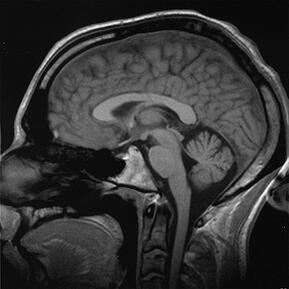

Characteristically, strokes have been known to affect mental abilities like information processing speed or attention, but not necessarily memory loss. To test the new theory, researchers conducted a study with over 650 dementia-free people aged 65 or older. The subjects were given MRI brain scans and took tests to measure their memory, language, information processing speed and visual perception. Researchers looked at the MRIs for evidence of silent strokes, which show up as dark holes indicating tissue loss. Of the 658 people tested, 174 were found to have had strokes. Those 174 performed worse on memory tests irrespective of how large their hippocampus was, though silent strokes were linked with a smaller hippocampus size.

Dr. Brickman said: "Given that conditions like Alzheimer's disease are defined mainly by memory problems, our results may lead to further insight into what causes symptoms and the development of new interventions for prevention. Since silent strokes and the volume of the hippocampus appeared to be associated with memory loss separately in our study, our results also support stroke prevention as a means for staving off memory problems." In light of these new findings, patients worried about memory loss should make sure they and their doctors are thoroughly managing their vascular health in order to prevent cognitive decline. Silent strokes are potentially preventable, and Dr. Brickman advises people to eat healthfully as well as take diabetes and high blood pressure medication (if needed) to maintain their blood vessel health.